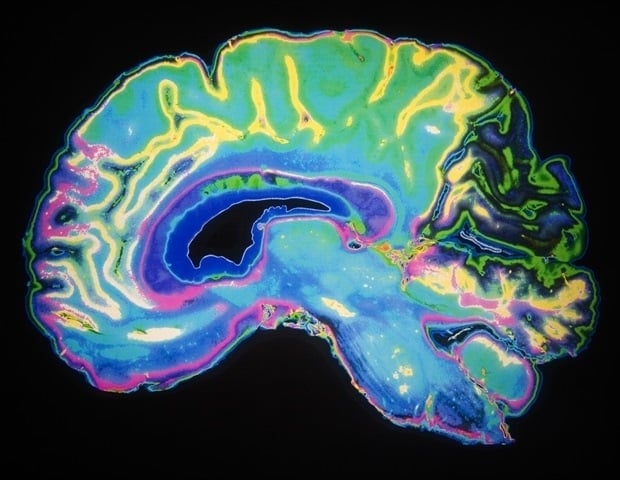

Les personnes atteintes d’encéphalomyélite myalgique/syndrome de fatigue chronique (EM/SFC) et de COVID long subissent une perturbation de leur connectivité cérébrale au cours d’une tâche mentalement exigeante.

La nouvelle recherche de l’Université Griffith, publiée aujourd’hui, a utilisé la technologie IRM à champ ultra-élevé pour étudier la réduction significative de la connectivité cérébrale dans des parties spécifiques du cerveau.

Les analyses montrent des changements dans les régions du cerveau qui peuvent contribuer à des difficultés cognitives telles que des problèmes de mémoire, des difficultés de concentration et une réflexion plus lente. »